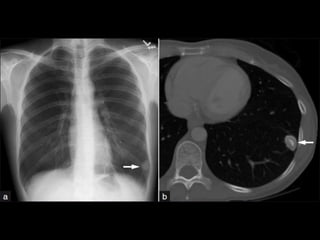

CT Angiogram Sign